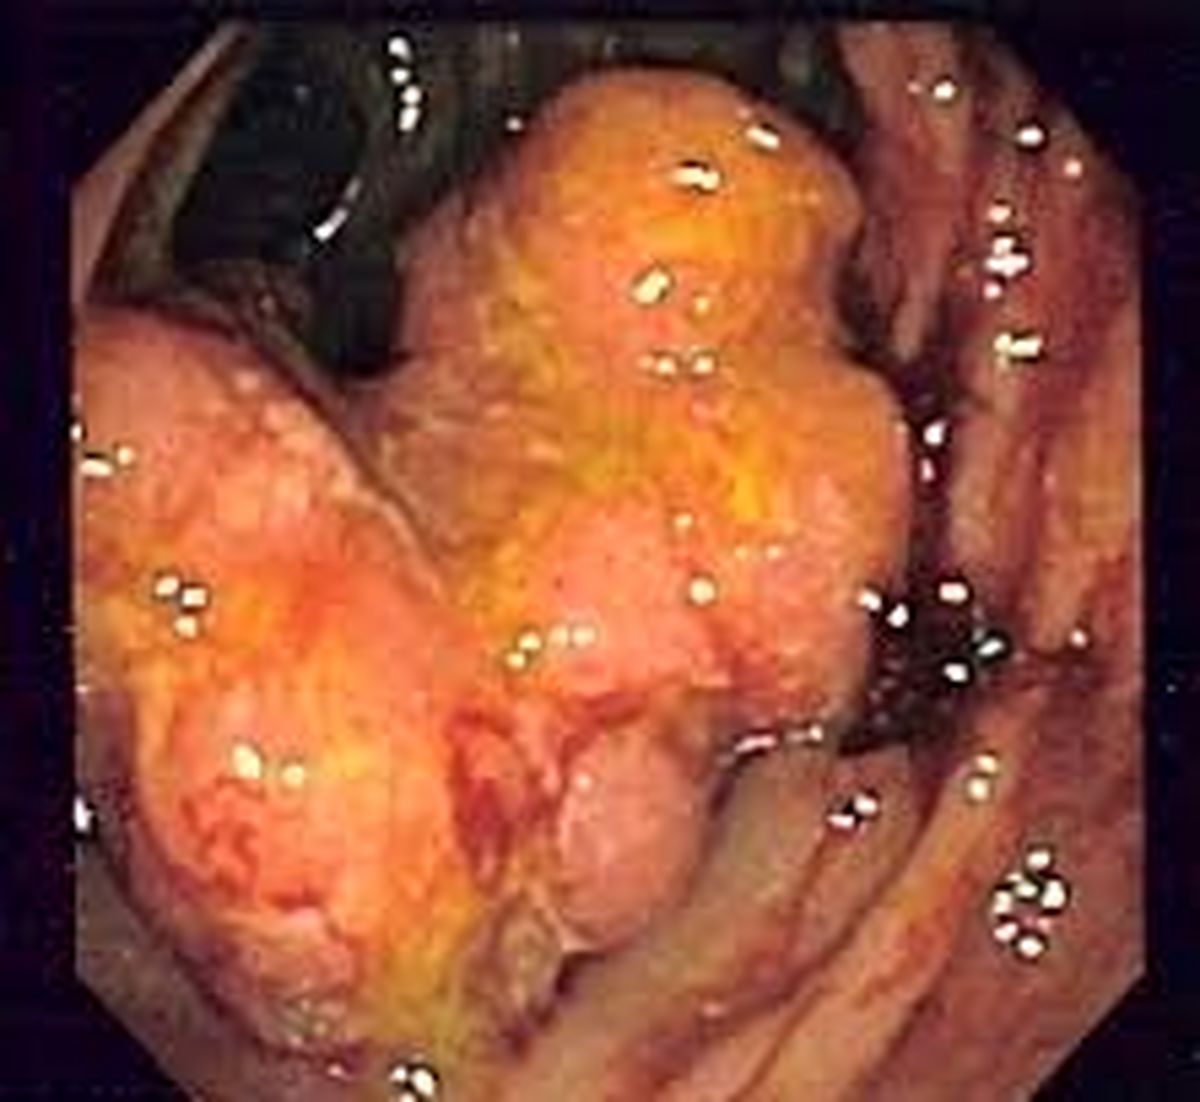

دکتر مونا ملک زاده مغانی در گفت و گو با روابط عمومی دانشگاه علوم پزشکی شهیدبهشتی با اشاره به این که سرطان روده بزرگ یا سرطان کولون و یا سرطان رکتوم به رشد توده های سرطانی در روده بزرگ گفته می شود از شیوع بالای این سرطان در دنیا خبر داد.

عضو هیئت علمی دانشگاه کلونوسکوپی را خصوصا در مراحل اولیه بیماری مهمترین راه تشخیص سرطان روده دانست وانجام کلونوسکوپی دوره ای در افراد بالای ۴۵ سال را مورد تاکید قرار داد.

این متخصص پرتودرمانی بررسی ضایعات در محدوده روده را ضروری دانست وادامه داد: ضایعات دربرخی اوقات با تشخیص قطعی توده سرطانی مشخص می شوند.